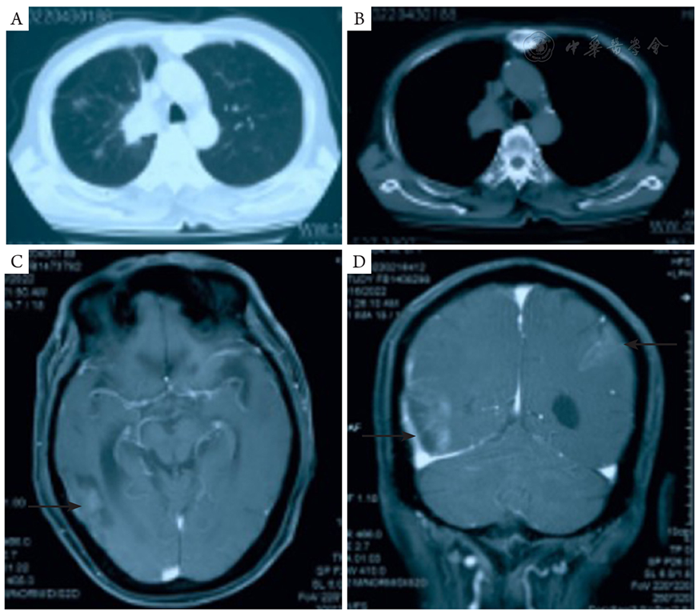

图1 患者入院时的胸部强化CT及头颅MRI检查。A,B:胸部CT示右肺上叶及右肺门区病变,最大横截面积约89 mm × 53 mm;C,D:头颅MRI示右侧颞枕叶富血供肿瘤,左侧顶叶异常强化。CT:计算机断层扫描;MRI:磁共振